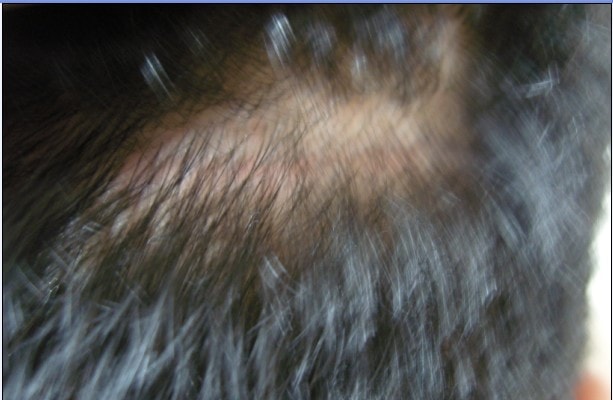

6) 术后后脑状态

3) 后面的头发很难拍照 用手掀开姿势

只有细看才能看到细细的、微红的实线。

(缝后脑勺的实力应该是世界第一吧)